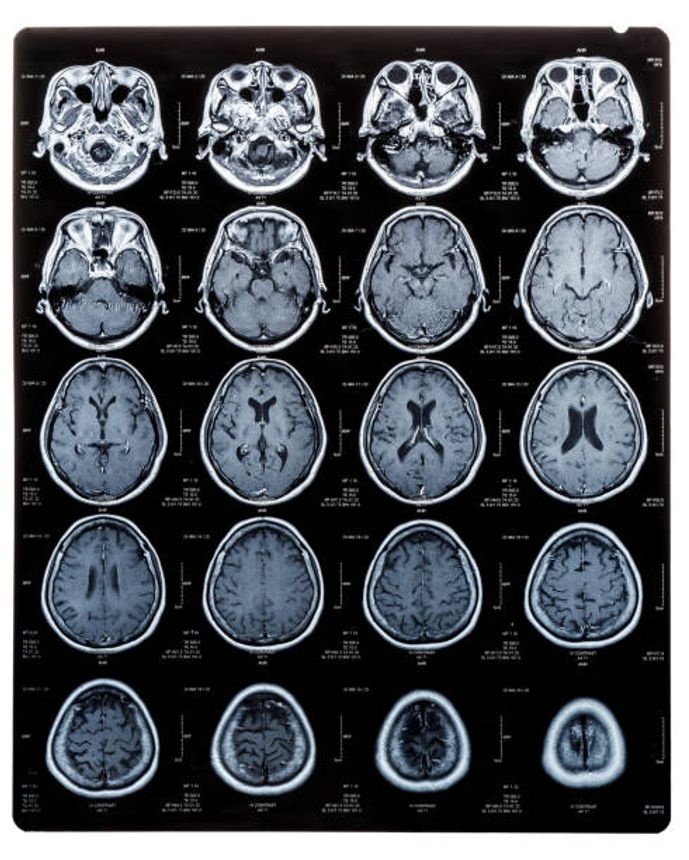

Dementia can affect a person’s ability to make decisions because it can affect the parts of the brain involved in remembering, understanding and processing information. However, because the disease is progressive, it is likely that a person’s capacity will reduce over time, and the rate and the extent to which this happens will depend on the individual and the type of dementia they have.